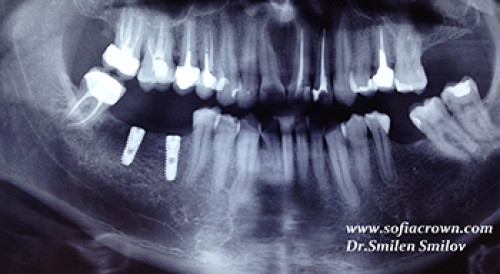

Клиничен случай имплантология 46 47

Поставени два зъбни импланта в областта на 46 и 47 в долна челюст.